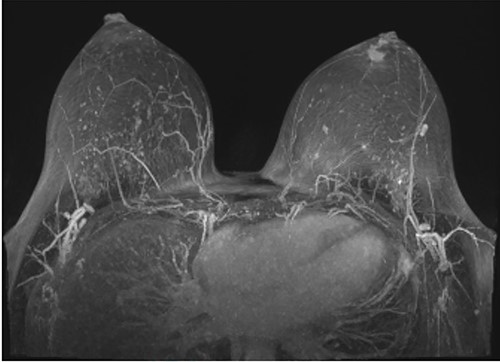

Following initial review, the patient was referred for a magnetic resonance image (MRI) which demonstrated an indeterminate retro-areolar lesion in the left breast (Fig. 2). A targeted ultrasound and core needle biopsy also showed active chronic periductal, interlobular and interstitial inflammation with focal duct ectasia consistent with Breast Imaging Reporting and Database System (BI-RADS) score of 2. Histological analysis showed predominant eosinophilic infiltrate (Fig. 3). There was no evidence of granulomatous inflammation or malignancy and staining for fungal elements and mycobacterium was also negative. A biopsy of the adjacent skin showed ongoing periductal and interstitial chronic inflammatory cell infiltrate with focal abscess formation (Fig. 4).